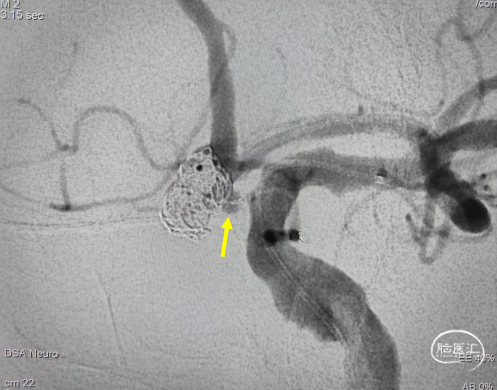

造影示瘤颈处子瘤仍显影,弹簧圈未进入子瘤,故再次用微导丝导引微导管超至子瘤口。(图示微导管头端位置)

填入2mm*4cm、1.5mm*3cm 通桥凤®弹簧圈2枚,弹簧圈顺利填入子瘤。

术后正侧位,动脉瘤栓塞满意,载瘤动脉血流通畅,未行支架或微导管辅助栓塞。